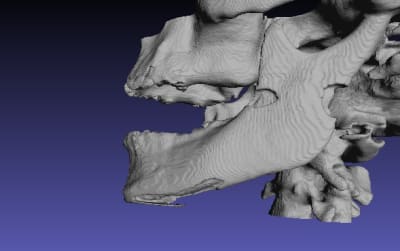

qu'est ce que vous pensez de ce guide, à mon avis il ne nécessite ni irrigation interne ni pins de rétention ( s'il est supra osseux) car rien qu'à l'aide d'un petit coup de marteau il s'enfoncera très bien sur l'Os avec une tres grande précision grace à sa structure trabéculaire.

Je vous invite à voir les autres images sur la Dropbox car elles sont très volumineuses et je n'ai pas pu les importer sur eugenol.